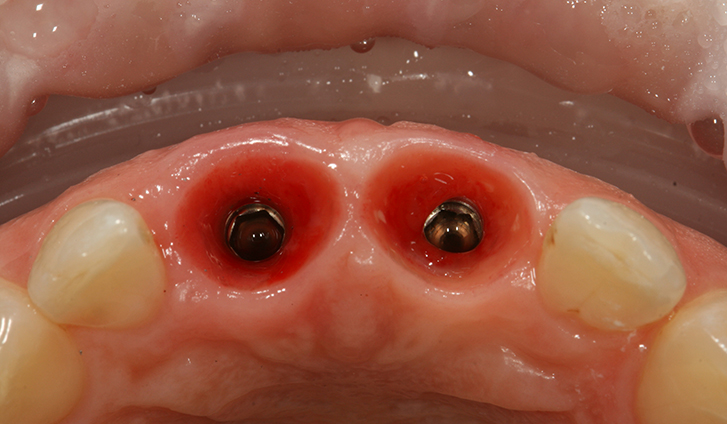

Одномоментная имплантация центральных резцов (сразу после удаления). С немедленной нагрузкой временными коронками.